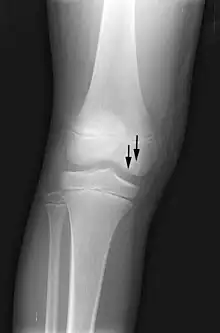

Front X-ray of right knee of an adolescent (epiphyseal plates are open): arrows point to avascular necrosis and developing osteochondritis dissecans in the outer medial condyle of femur

In the early stages, bone scintigraphy and MRI are the preferred diagnostic tools.[11]

X-ray images of avascular necrosis in the early stages usually appear normal. In later stages it appears relatively more radio-opaque due to the nearby living bone becoming resorbed secondary to reactive hyperemia.[2] The necrotic bone itself does not show increased radiographic opacity, as dead bone cannot undergo bone resorption which is carried out by living osteoclasts.[2]